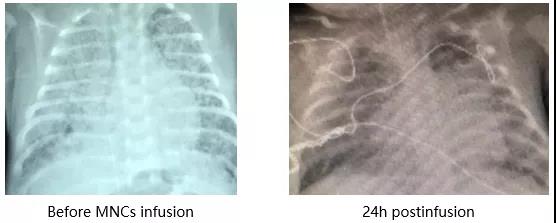

2. 胎龄25+w,外院诊断重度BPD,生后120天仍未能撤离呼吸机入院。

输注脐带血后气道高反应性缓解。